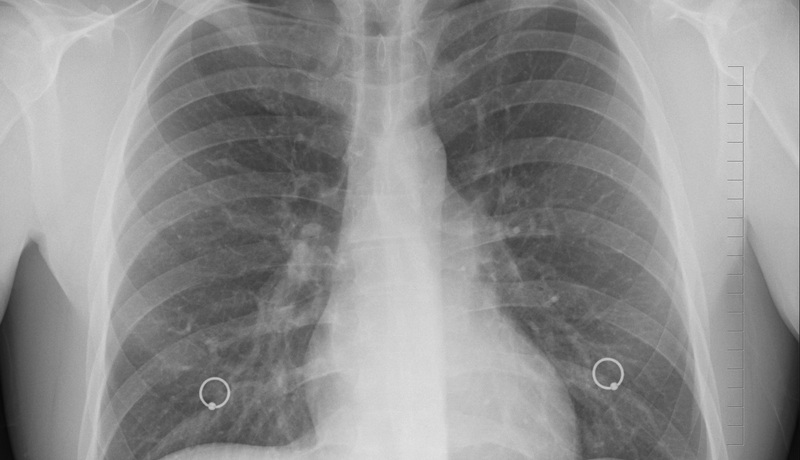

Femeile rămân cu sechele mai mari după infectarea cu Covid-19. Cele trei efecte prelungite constatate